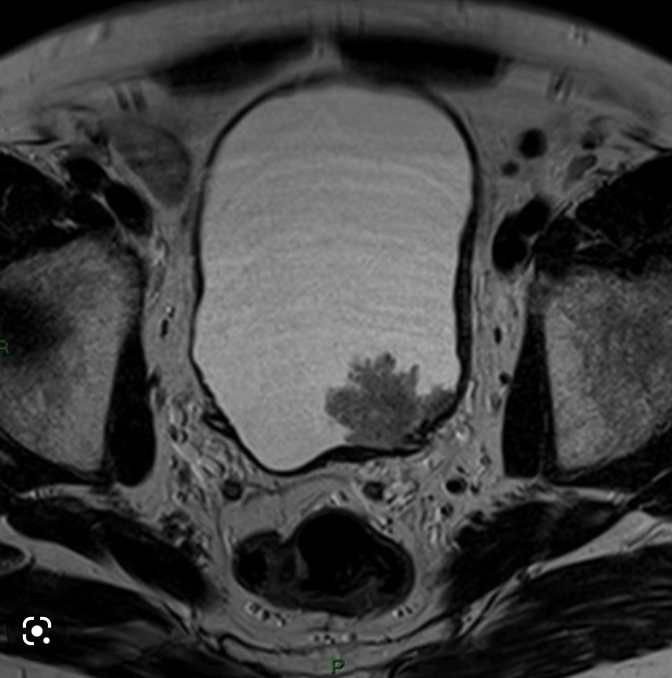

16

Q

40 y/o F

A

Think bladder leiomyoma

Note: Smooth, solid, homogenous soft tissue mass in the region of the trigone (most common location).